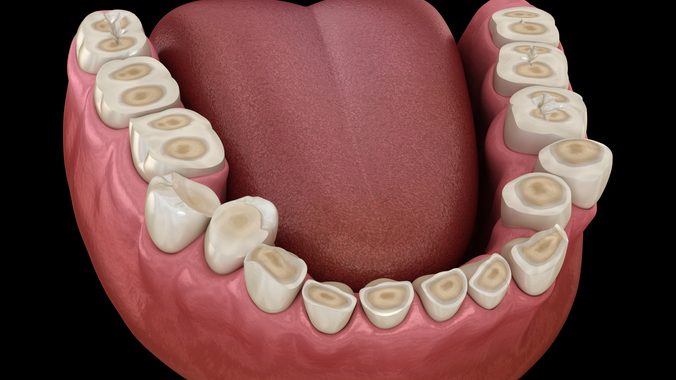

Réhabilitation globale des dents usées

Certains patients présentent des dents usées. En effet, les dents s’usent physiologiquement dans le temps du fait de nos différents cycles masticatoires. Seulement, dans certaines conditions l’usure peut devenir pathologique et entrainer une destruction rapide des dents. Cela peut être du a un brossage traumatisant, a des attaques acides (Consommations excessives de soda/agrumes/citron, de reflux gastro-oesophagien etc) mais aussi à un « grincement » des dents, qu’on appelle aussi bruxisme. Dans des stades initiaux, une surveillance et une correction de l’étiologie peut être mise en place. Cependant, lorsque l’usure est prononcée, qu’elle handicape sur le point de vue esthétique ou fonctionnel (sensibilités), une réhabilitation globale doit être faite afin de recréer l’émail perdu avec de la céramique.

Dans les 4 cas cliniques ci dessous, une usure pathologique a été traitée par un ajout de céramique. Après une analyse esthétique, des photographies du visage et des empreintes numériques, un projet esthétique est essayé en bouche, sans toucher aux dents. Si le projet est validé par le patient et le praticien, le plan « d’architecte » est établi : La réhabilitation peut alors commencer. Afin de rallonger les dents usées, des restaurations en céramiques sont donc collées sur toutes les dents, afin de retrouver un aspect naturel.